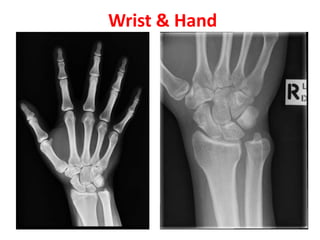

Wrist & Hand

Hand and Wrist

Appearance(Years)

• 1st – lower end radius, capitate,

hamate

• 2nd – Head of 2,3,4,5th

metacarpal, bases of proximal

phalanges

• 3rd – Triquetral, base of first

metacarpal, middle and

terminal phalanges

• 4th – lunate

• 5th – trapezium,trapezoid,

scaphoid

• 6th – lower end of ulna

• 12th- Pisiform

Fusion(Years)

• 17th – base of first

metacarpal

• 18th – epiphysis of

metacarpals, phalanges

and lower end of ulna

• 19th – lower end of

radius